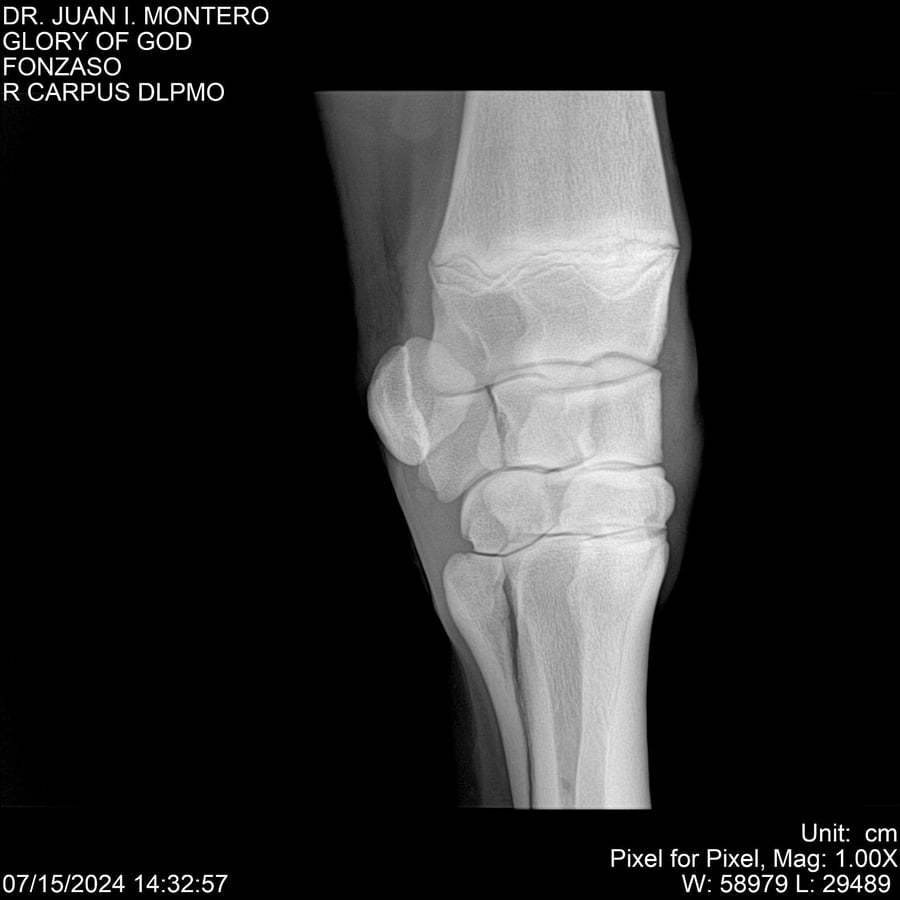

LOTE 10, GLORY OF GOD 🔥 🔥 🔥 Lote Anterior Volver al remate Lote Siguiente Ficha Contacto Montevideo - Ficha del Lote Identificador: #281389 Categoría: Yeguarizos Montevideo - 115 Visualizaciones ClicData Contacto Empresa: Abelenda N. R., Walter Hugo Nombre*: Teléfono* : E-mail* : Mensaje Enviar Registrese gratis Este contenido Exclusivo está disponible sólo para usuarios registrados Ingresar